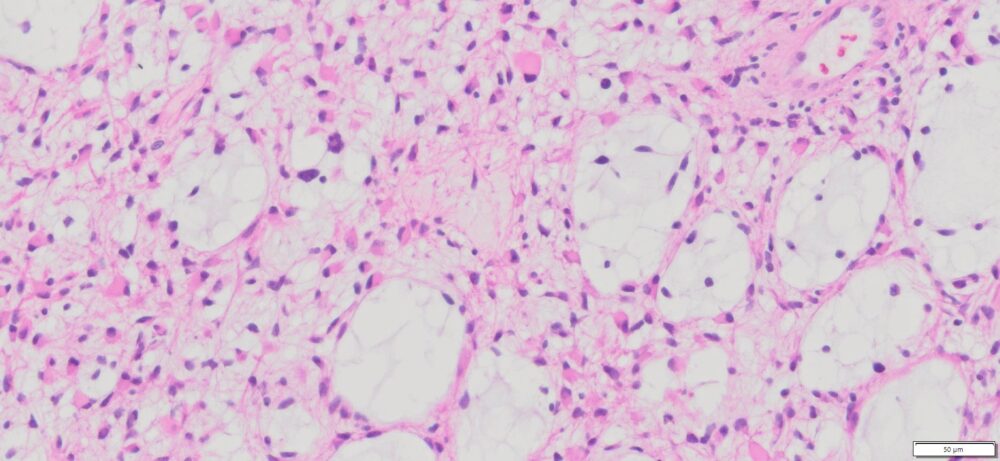

| Tissue | Pathology Diagnosis | Gender/Age (year) | % Tumor area | Tumor Grade | TMN Stage | IHC Data |

| Human Brain | Human Brain Astrocytoma | Male/36 | 95% | IV | NA | IDH1 (+), ATRX (-), P53 (-), Ki67 (+30%) |

Images for H&E Stain and IHC